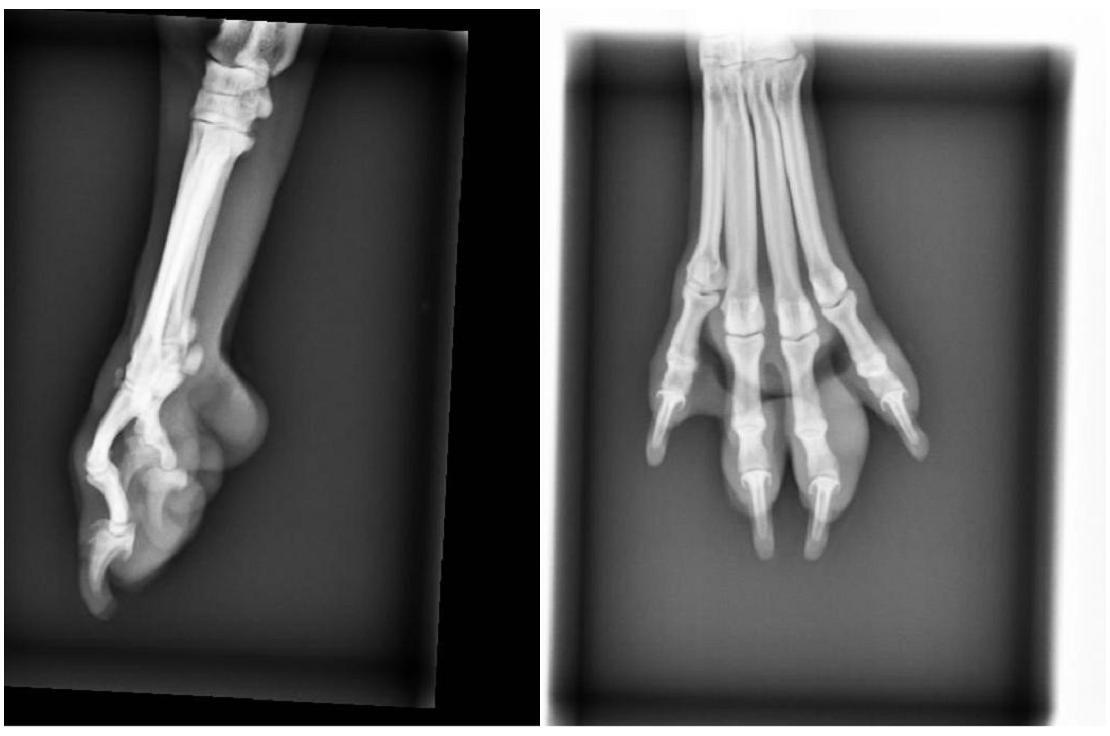

傷口位於左前肢內側穿刺傷.外側潰爛

還好沒傷到骨頭.

但是傷口真的很深.

醫師研判應該是東西插入造成的,

還好發現得早免於太嚴重會導致截肢,

2.X-RAY 400*2